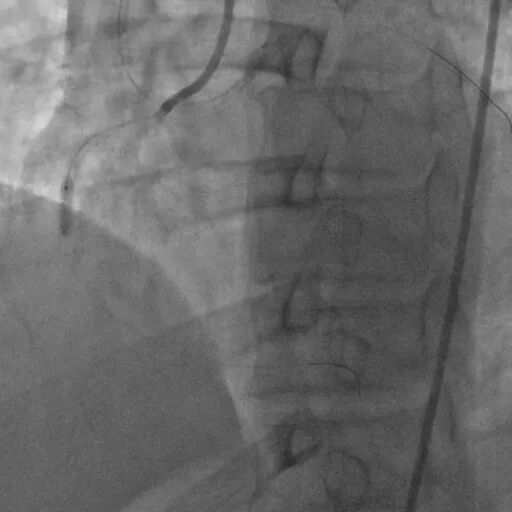

治疗方案(介入治疗·冠脉造影)

LCX近段30%狭窄,OM1 80%狭窄,OM2 90%狭窄,LAD近段100%狭窄,D1高位发出,80%狭窄。

冠脉造影

RCA中段支架内增生 80%,PL 100%。

双侧造影明确LAD开口位置和临近血管关系。